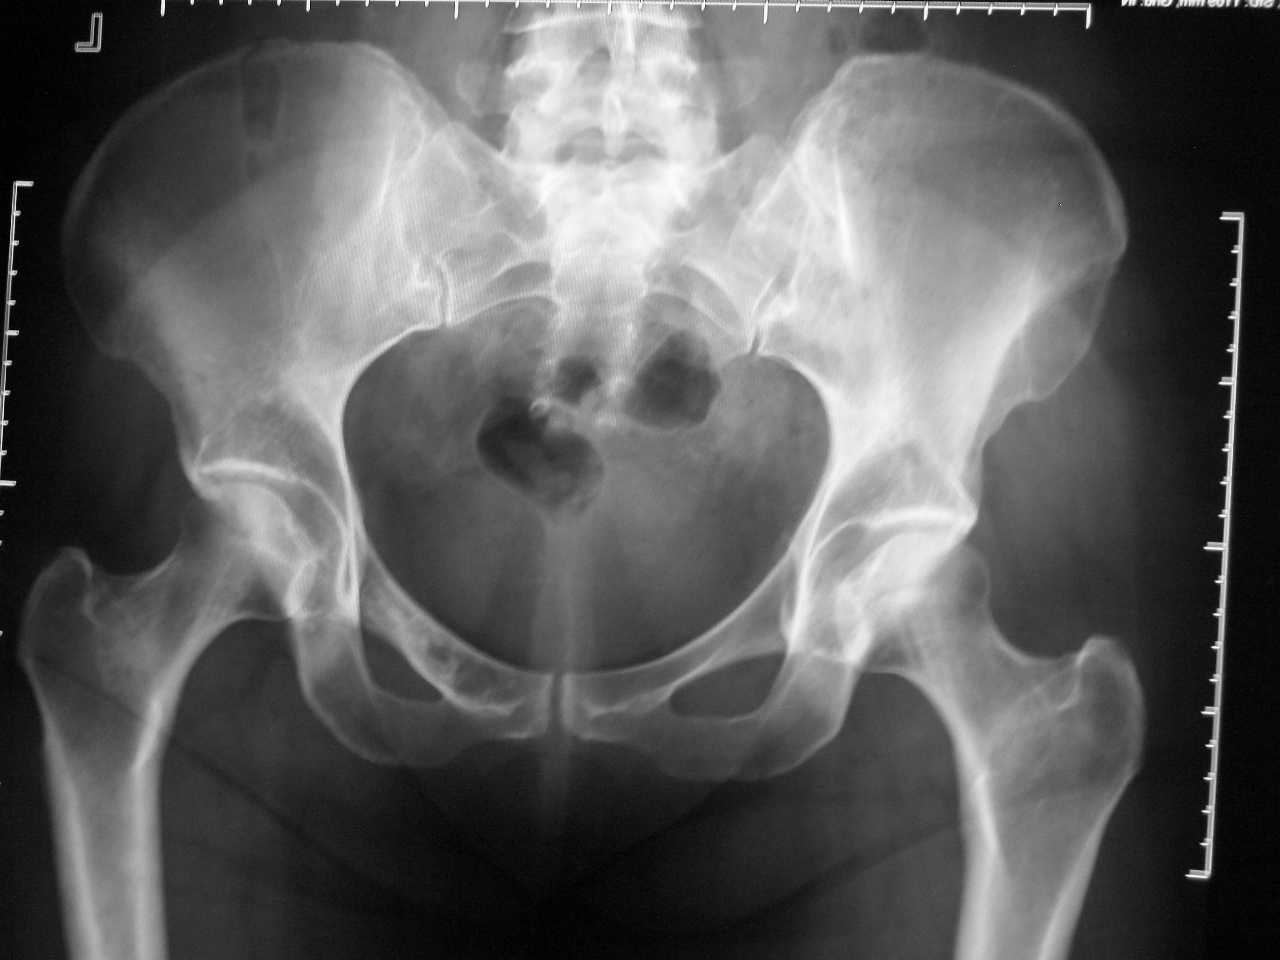

Мнения по поводу приложенного снимка разделились,

а что вы скажете ,уважаемые коллеги?

Похоже, на снимке изображен таз. Были другие мнения?

Мнения другие есть.Больная 47 лет,семь лет назад сорвалась с ног на таз

перелазая ограждение.

Сейчас боли в крестце не постоянные ,боли в животе тоже не

всегда,задержки мочи и стула,увеличения обьема живота (определяет по

одежде).

Есть мнение о переломе крестца и копчика,есть мнение о остеолитическом

мтс.В тазу хорошо просматриваются изменения в лонной кости справа.

Есть мнение и о воспалительном процессе в организме,с учетом состояния

костей.

Возможно и был перелом дистальной части крестца но он клинически незначим. Стоит сделать прицельный жесткий снимок лонных костей. И "прокрутить" по возрастающей: ОАК, ОАМ, ЩФ,общий белок, гинеколог,невролог (синдром сдавления конского хвоста) Ректо и ирригоскопия, М- градиент. РКТ.

На КТ :деструкция передней пластинки крестца и деструкция лоной кости кости справа под вопросом.

Деструкцкия лонной кости, а особенно деструкция передней пластинки крестца - признаки не перелома, а процесса, возможно, неопластического. Проводилось ли гистологическое обследование после НАМ с придатками, когда было обследование молочных желез, щиовидной железы (включая доп. методы - УЗИ, маммография)? Онкомаркеры смотрели? Каков анамнез, габитус пациентки? Блин, одни вопросы.